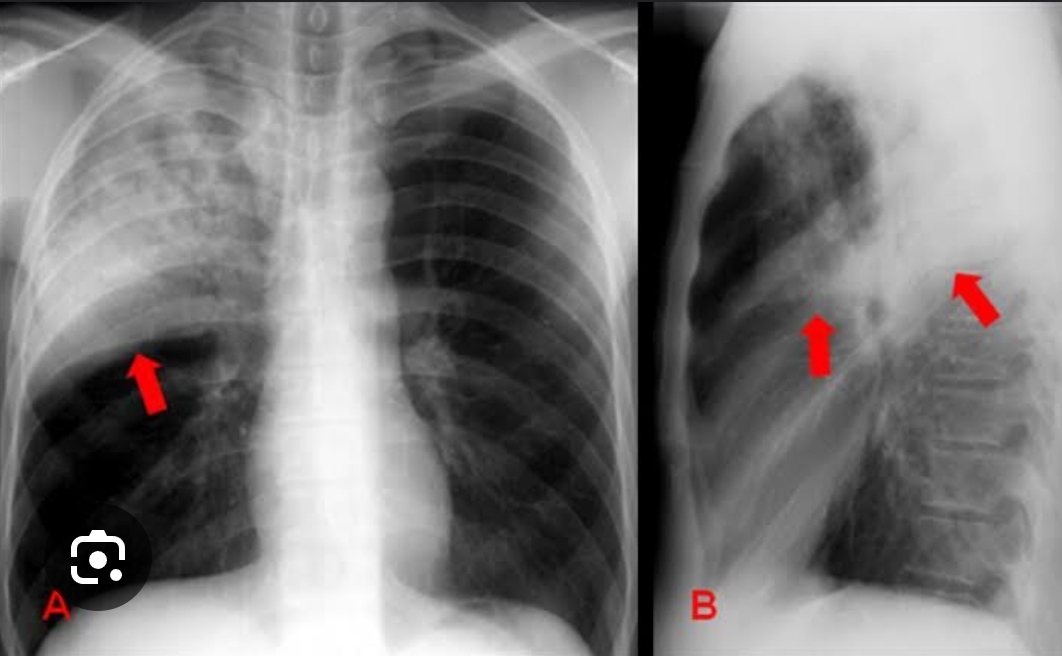

Padrões de aumento de atenuação focal?(branco)

A

Consolidação: preenchimento alveolar não delimitado + volume preservado

Atelectasia: colabamento alveolar + volume diminuído + retração da traqueia e mediastino para lado colabado .

Nódulo/massa: sólido bem

delimitada.

Como se dá o padrão de consolidação?

Broncograma aéreo ( contorno dos brônquios) + radiopacidade mal delimitado + volume preservado